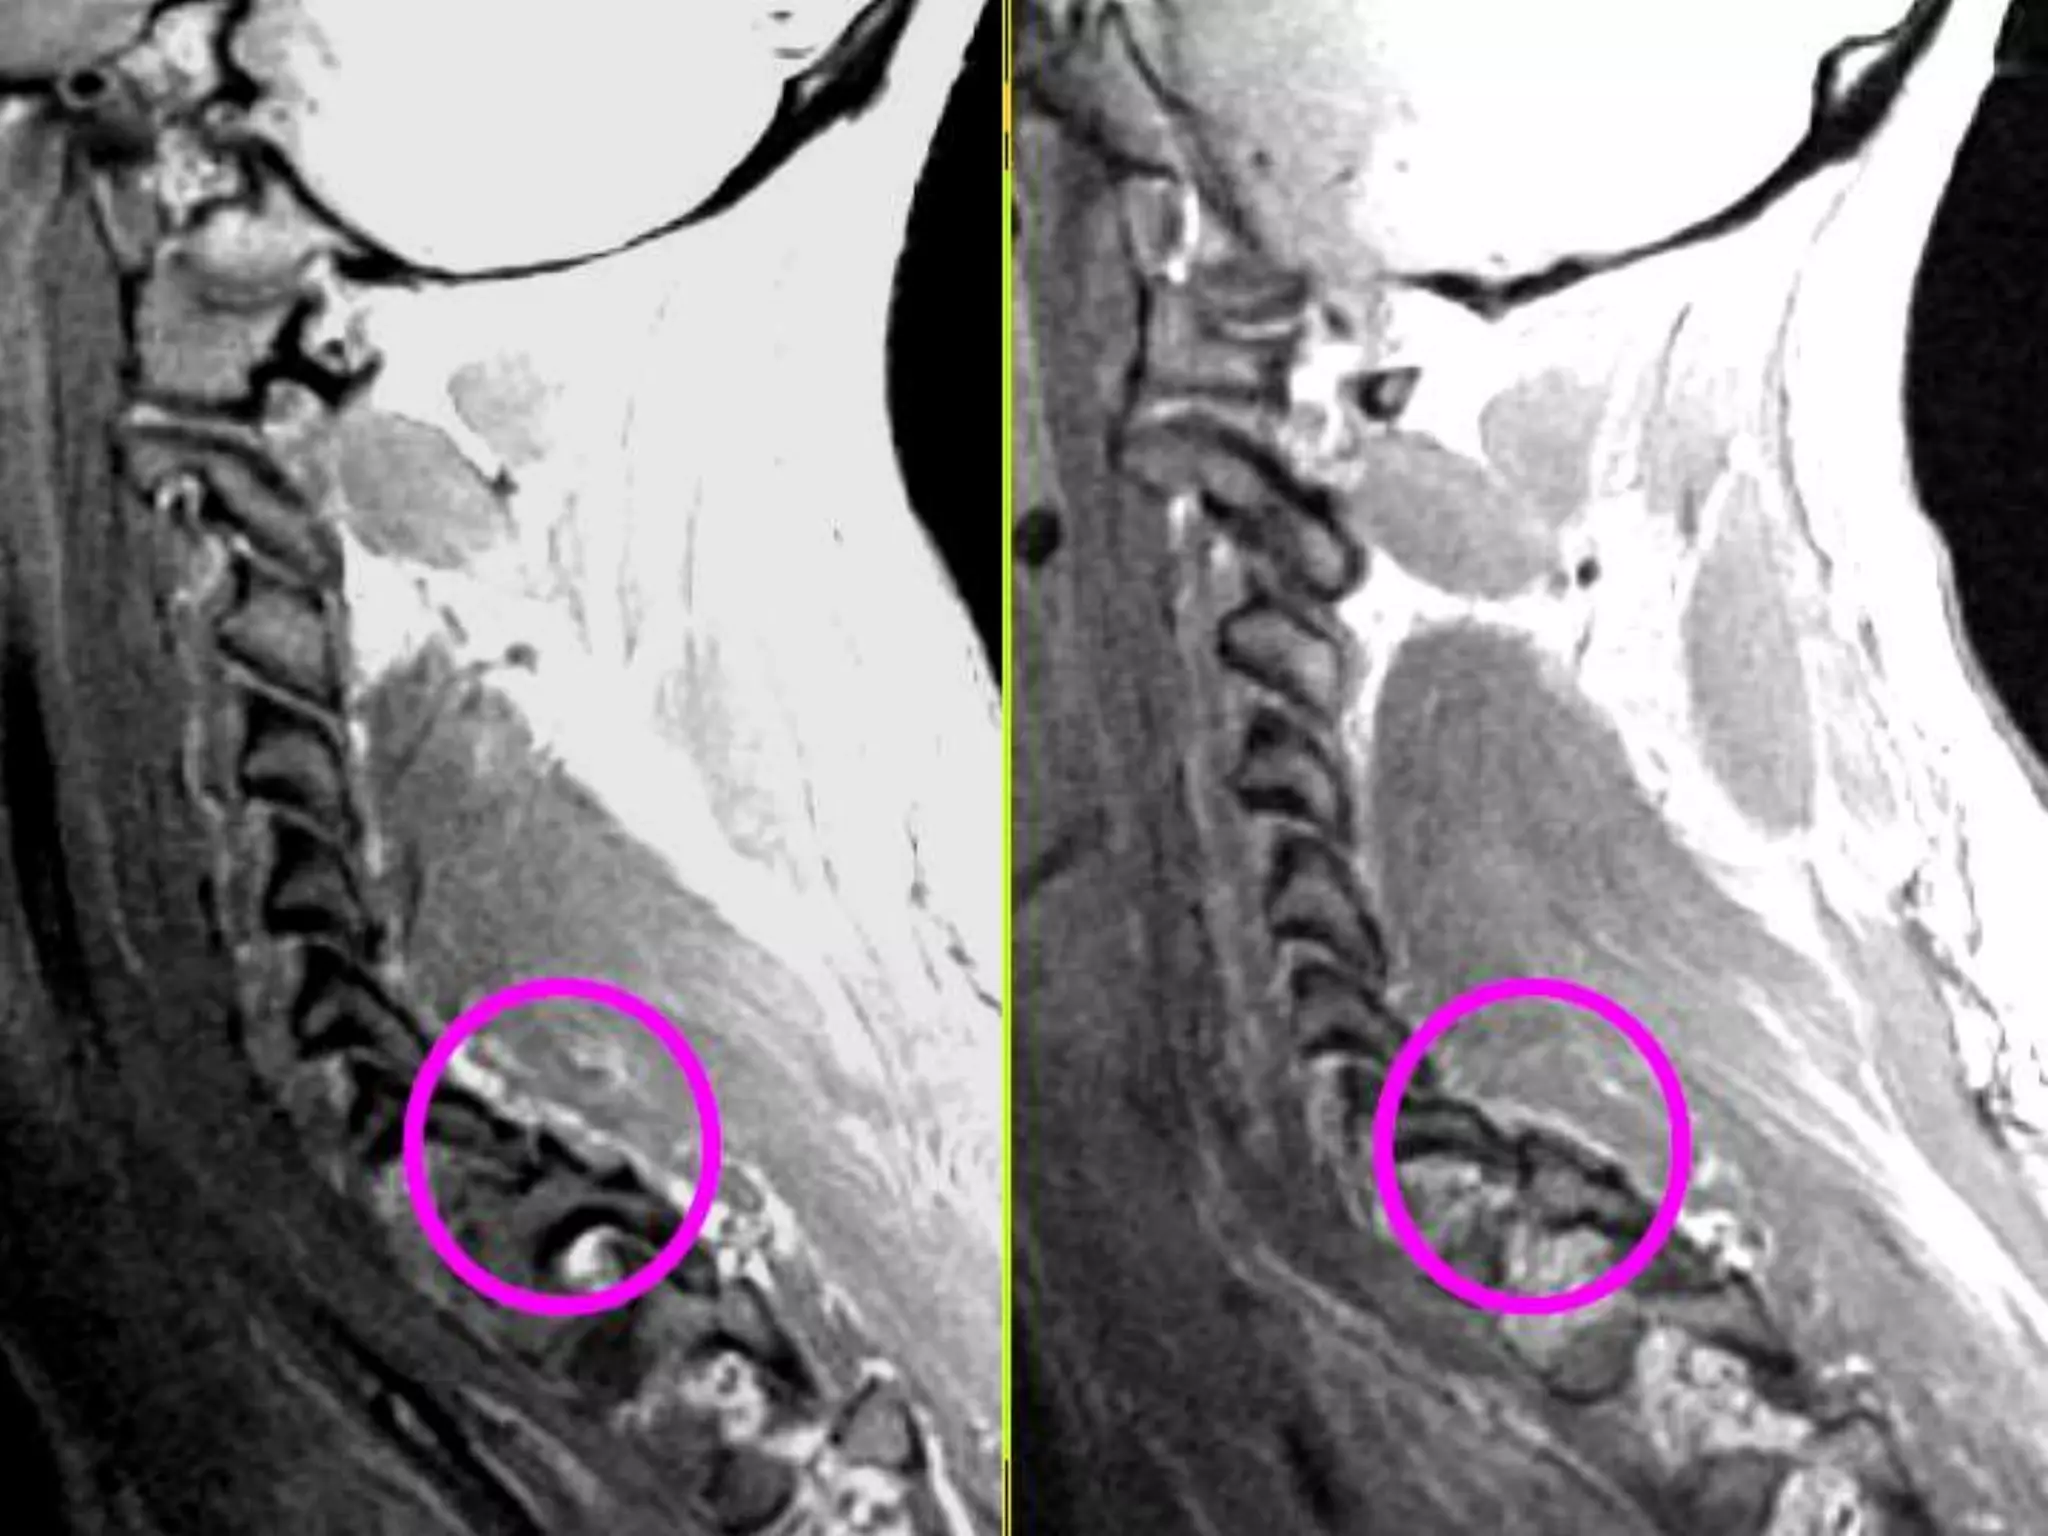

Sagittal T2W

image of 23yr

old male

showing burst

fracture with

anterior

wedging(arrow)

of L1 vertebra.